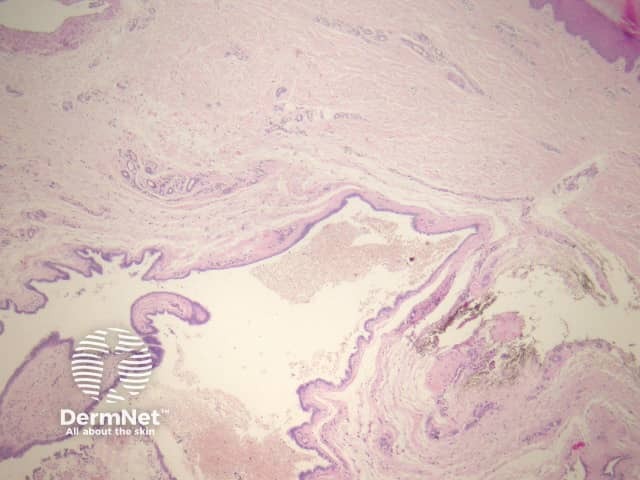

In cutaneous ciliated cyst, sections show a dermally based cyst (figure 1) which is often filled with secretions and debris (figure 2). The cyst is lined by a cuboidal or columnar epithelium which is ciliated (figures 3 and 4, arrows indicate cilia). There may be areas of squamous metaplasia.

Figure 1